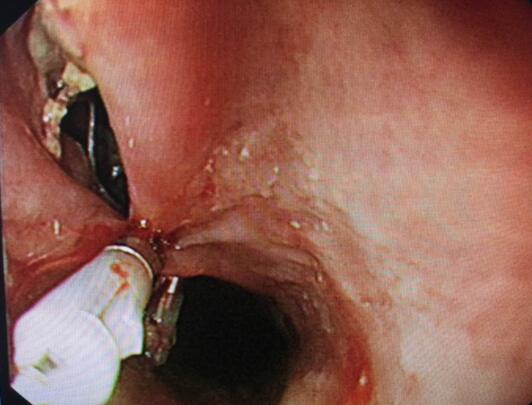

内镜中心王莹副主任考虑到患者病情复杂且高龄,不具备急诊外科手术条件,在确保患者安全情况下行内镜下异物钳取术、钛夹封闭损伤治疗。术中观察到梭形枣核嵌顿于患者食管上端,一侧食管壁可见纵形全层伤口,损伤非常严重。王主任克服困难,以她熟练的操作最终将异物顺利取出。

异物

食道损伤

钛夹逐渐夹闭损伤